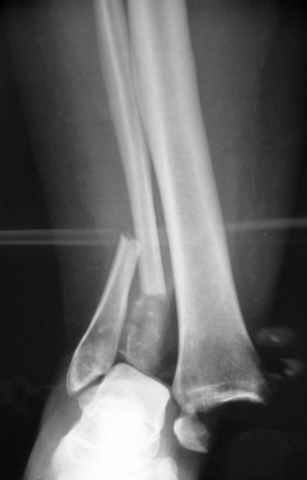

Pilon fracture:

-Появляется ориентир и остов, на чем можно строить восстановление, почему сперва малоберцовую, впервые обьяснили и описали (Pylon type and Ankle fractures) в середине 50х Rienau и Gay.

Восстановливая длину и ротацию малоберцовой кости, затем относительно легче произвести реставрацию остальных элементов перелома дистального эпиметафиза болшеберцовой кости.

где исследования на трупах показали, что малоберцовая кость участвует в стабильности голеностопного сустава, поддерживая наклон тарана (talar tilt) за счет связок. После ознакомления работой Ramsey в ортопедию ввели термин "при переломах голеностопного сустава смещенная

таранная кость следует за малоберцовой костью" т.е. связка не рвется, а тянет таран за собой, поэтому восстановление малоберцовой кости в

первую очередь, затем остальных элементов - стал классическим при лечении данной патолгии. Латеральная колонна (столб), дистальный

конец малоберцевой кости, к нему прикрепляется латеральный суставной фрагмент дистального эпиметафиза большеберцовой кости (как на снимке)

и таранная кость, которые при репозиции малоберцовой кости репонируются автоматически.

Традиционная техники АО, открытая, с точной репозицией суставной поверхности и жесткой фиксацией, из-за серёзных осложнений, которые

заканчивались ампутацией, уходит в прошлое.

Техника сегодня более щадящая, временные несложные аппараты наружной фиксации: Spanning 2 pin ExFix, Traveling traction для лигаментотаксиса, иначе сокращенные мягкие ткани невозможно восстановить позже.

За последнее 10-12 лет после стабилизации малоберцовой кости, стали применять более усовершенный, сложный, хорошо вам известный метод

Илизарова (кстати наряду с тибиал плато, пилон является одним из показанием по применению аппарата Илизарова при травмах) или Hybrid

Fixator, из минимальных доступов комбинированный метод для восстановления суставной поверхности-фиксация каннулированными

шурупами, создания жесткой системы фиксации до сращения перелома, защита от вальгусной деформации и на место образовавщегося метафизарного дефекта- костная пластика ауто костью или его

синтетические заменители, это сегодняшная тактика лечения.